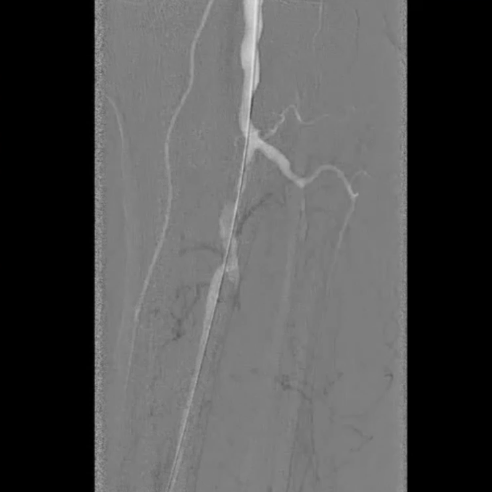

造影评估与通路建立

造影显示左侧胫腓干动脉闭塞,胫后动脉通过侧支循环显影,左侧腓动脉及胫前动脉全程闭塞。

先尝试顺行穿刺,导丝进入内膜下未能成功通过;改为逆行穿刺胫后动脉,导入V18导丝,采用Safari技术(逆行导丝通过闭塞段与近端导管对接)建立工作轨道。